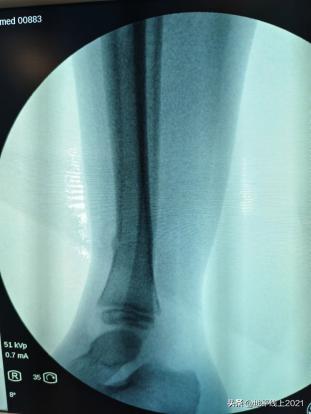

再看一个下肢的案例,同样是在麻醉下纠正,用一个管型树脂石膏固定。